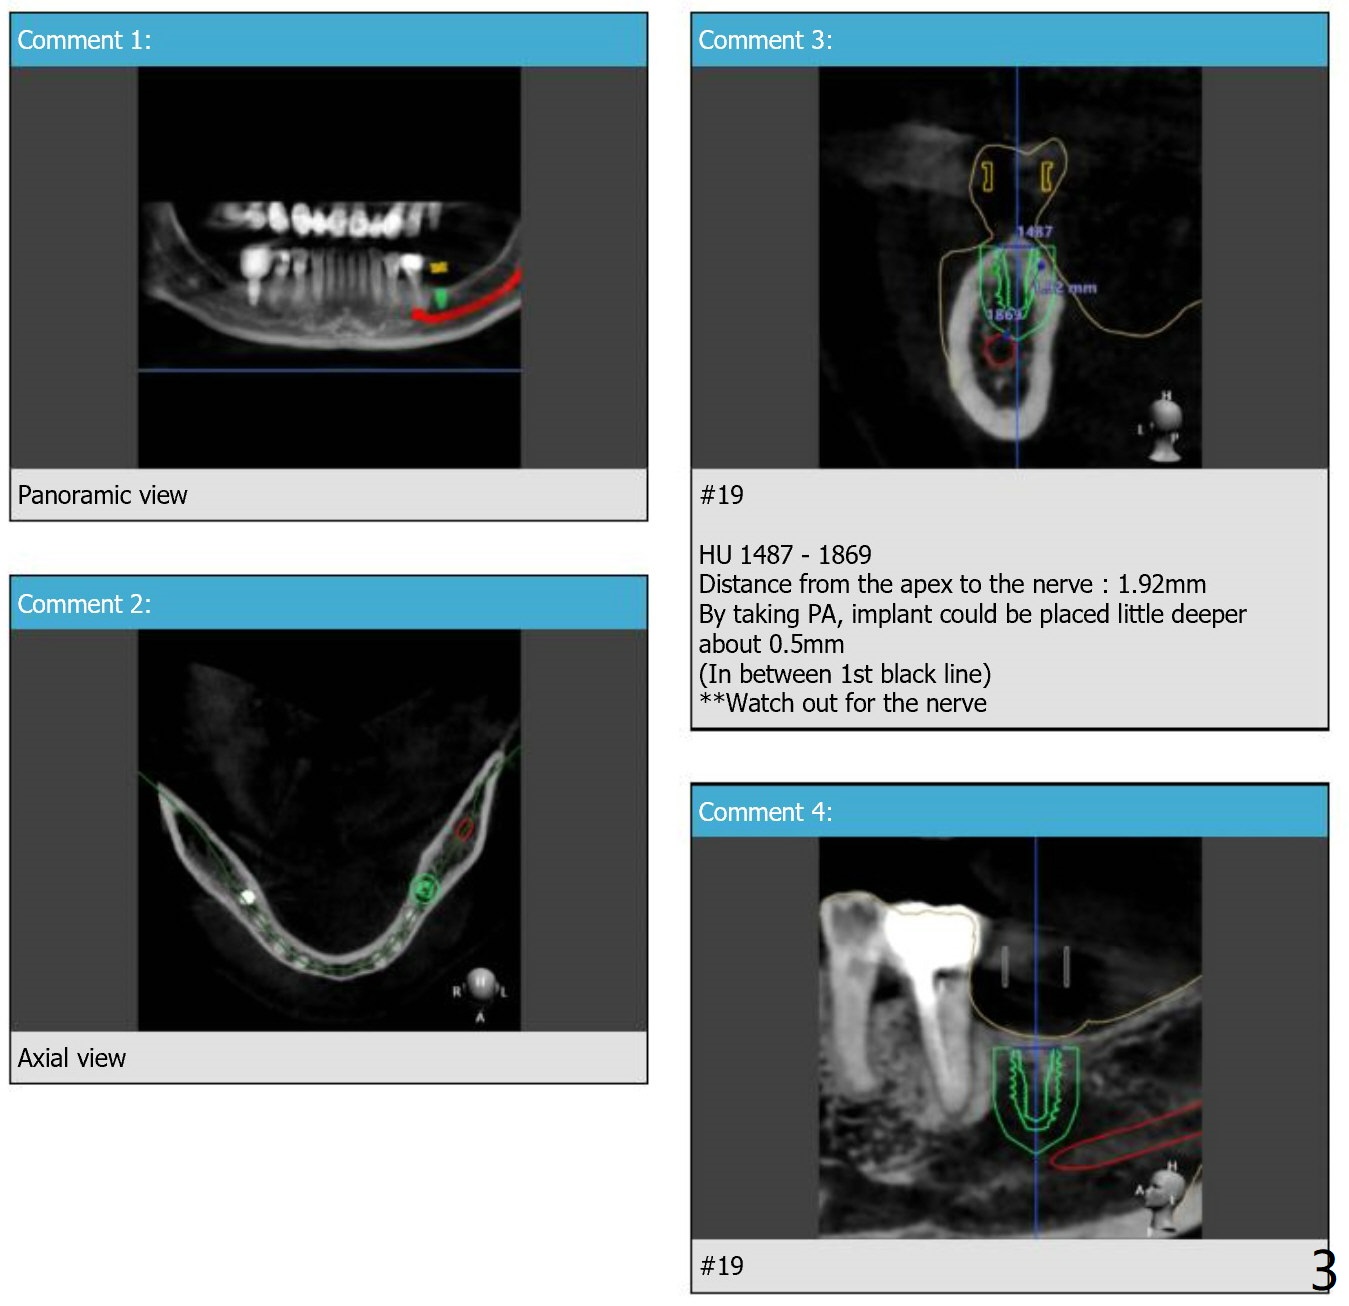

When is the best time to take PA for #19 osteotomy?  2.2x7.3 mm drill or 4.5x7.3 mm implant?  Can we take PA with the guide in place?  Thanks.

You do not have to worry during the osteotomy. I have kept the safety zone of 2mm at the apex. Only thing for the PA would be while placing implant with fixture driver. Remove the surgical guide and take PA when the bottom of first black line has met the metal sleeve top and when you think there's enough room to place implant little deeper based on the PA, you can rotate the fixture driver more to place deeply just little like 0.5mm (at the middle of first black line).